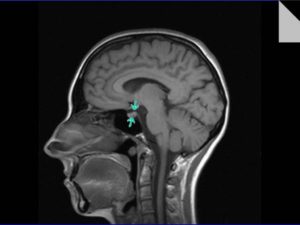

Ниже вы можете увидеть фото магнитно-резонансной томографии.

Чтобы лучше увидеть разницу между снимком МРТ с контрастом и без наведите курсор на фото и щёлкните по нему. В открывающимся окне вы сможете лучше рассмотреть отличия исследований.

Серия снимков МРТ головного мозга с применением контрастного вещества, сагиттальная и аксиальная проекции